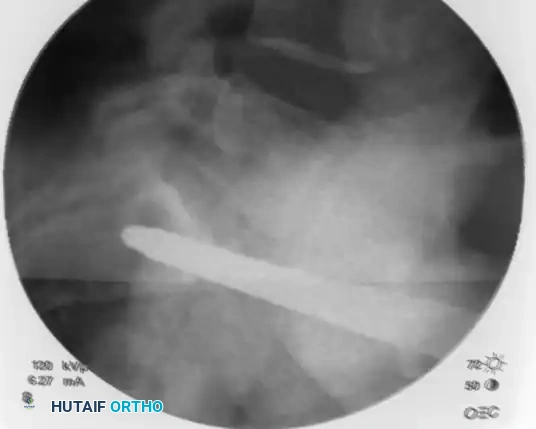

Select a cannulated, partially threaded cancellous screw (if compression across an SI joint or sacral fracture is desired) or a fully threaded screw (if acting purely as a position screw to prevent over-compression of a comminuted sacral fracture). Add a washer to prevent the screw head from sinking into the thin iliac cortex.

Advance the screw over the guidewire using a cannulated screwdriver.

Image

As the screw crosses the SI joint, continuously check its position on the inlet and outlet views to ensure the guidewire does not inadvertently advance and breach the anterior sacral cortex or spinal canal.

Once the screw is fully seated, perform a final fluoroscopic confirmation on the anteroposterior, inlet, and outlet views. The screw threads should have excellent purchase in the dense bone of the sacral body, and the fracture/dislocation should be anatomically reduced and compressed.